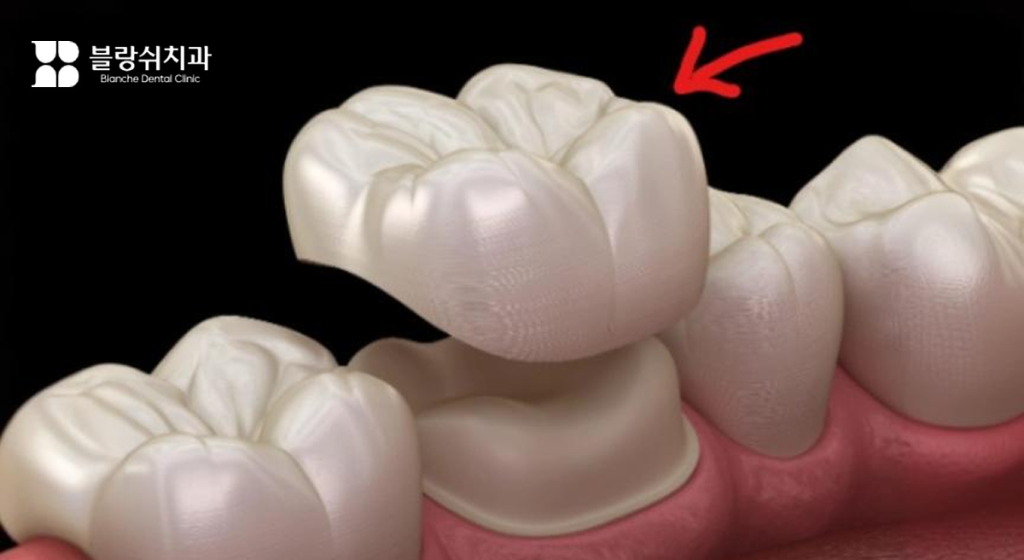

치아가 깨지거나 금이 간 경우 또는 신경치료까지 진행된 경우에는 크라운 치료를 하게 됩니다. 크라운 치료는 손상된 치아를 다듬은 뒤 치아 전체를 덮어 보호해 주는 보철 치료인데요. 재료에 따라 크라운 비용이 크게 달라질 수 있습니다.